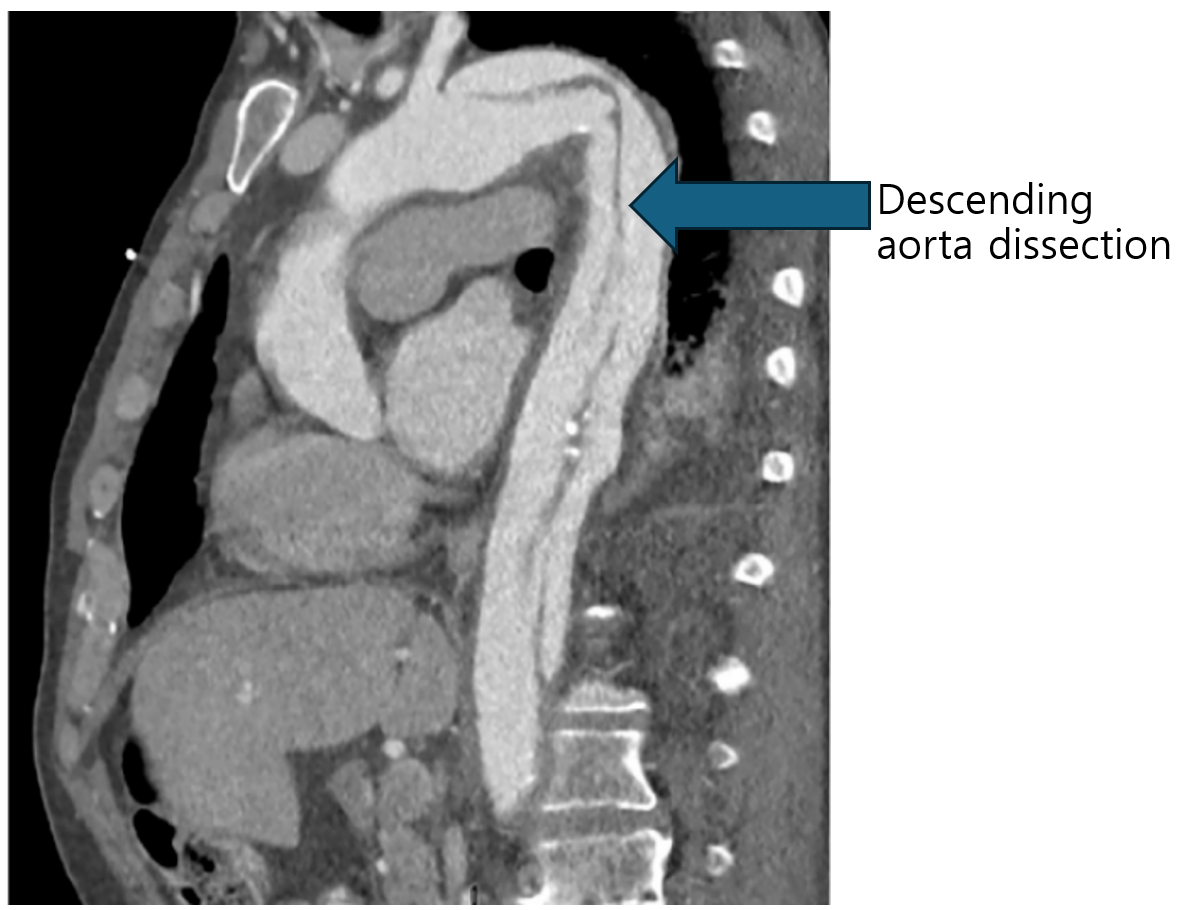

60세 남자가 30분 전부터 등이 아파서 응급실에 왔다. 사무실에서 근무하던 중 자정부터 등이 찢어질 듯한 통증이 발생하였다. 10년 전부터 혈압이 높았으나 약을 복용하지 않았다. 혈압 200/120 mmHg, 맥박 110회/분, 호흡 20회/분, 체온 36.5 ℃이다. 가슴 컴퓨터단층촬영 사진이다. 베타차단제 정맥 투여를 시작했다. 수축기 혈압의 목표치는?

Img | CT: Aortic intimal dissection membrane distal of the left subclavian artery |

Imp: 대동맥 박리(aortic dissection, AD), type B

Chest CT에서 대동맥 박리가 descending aorta에 관찰되므로 베타차단제로 BP/HR을 조절해야하며 수축기 혈압의 목표치는 100~120mmHg이다.

• Chest CT에서 descending aorta 내부의 intima tear이 관찰되므로 AD로 진단한다.

• 본 증례는 descending aorta만 침범한 stanford type B이고 등의 통증외 다른 합병증이 발생하지 않았으므로 약물 치료를 통해 BP와 HR을 조절해야한다.

• 대동맥 박리에서 SBP 목표치는 100~120mmHg이고 HR은 60~80회/분이다.